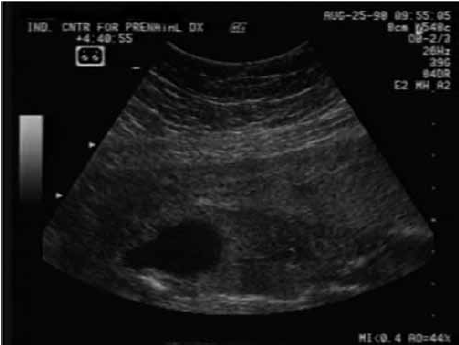

Paciente gestante, com 24 semanas e 4 dias de gestação, realiza ultrassonografia pré-natal que revela feto do sexo masculino, presença de hidronefrose bilateral, bexiga dilatada, com sinal do “buraco da fechadura”, conforme imagem a seguir:

O quadro apresentado é sugestivo de